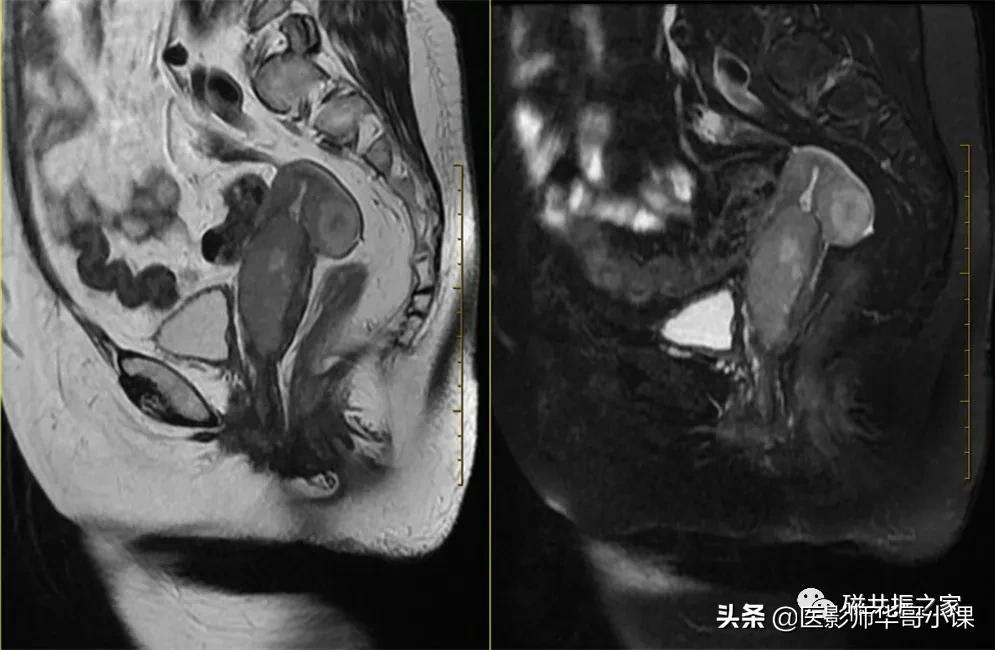

在横轴位和冠状位上定位。在横轴位上找到显示子宫体最大的层面,使定位线垂直于当前子宫内膜长轴,在冠状位上调整角度使定位线平行于子宫全长长轴(平行于子宫颈和子宫底中点的连线);如是宫颈病变,应以宫颈管为基准定位。左右扫描范围包括整个子宫,需包括整个病变范围。

矢状位是显示子宫全景较为理想的方位,该序列采用压脂或不压脂均可,但最好能做到小视野的高分辨率扫描。在T2WI上能清楚的显示子宫(绝经前)的四层结构。

在冠状位和矢状位上定位,在矢状位上找到显示子宫全景最好的层面,如需了解宫颈病变,使定位线垂直于宫颈管长轴(图A),如需了解子宫内膜病变,使定位线垂直于子宫内膜长轴(图B)。在冠状位调整角度使两侧对称扫描,扫描范围上至子宫上缘下至耻骨联合,需包括整个病变范围,如观察转移性病变需加大扫描范围。